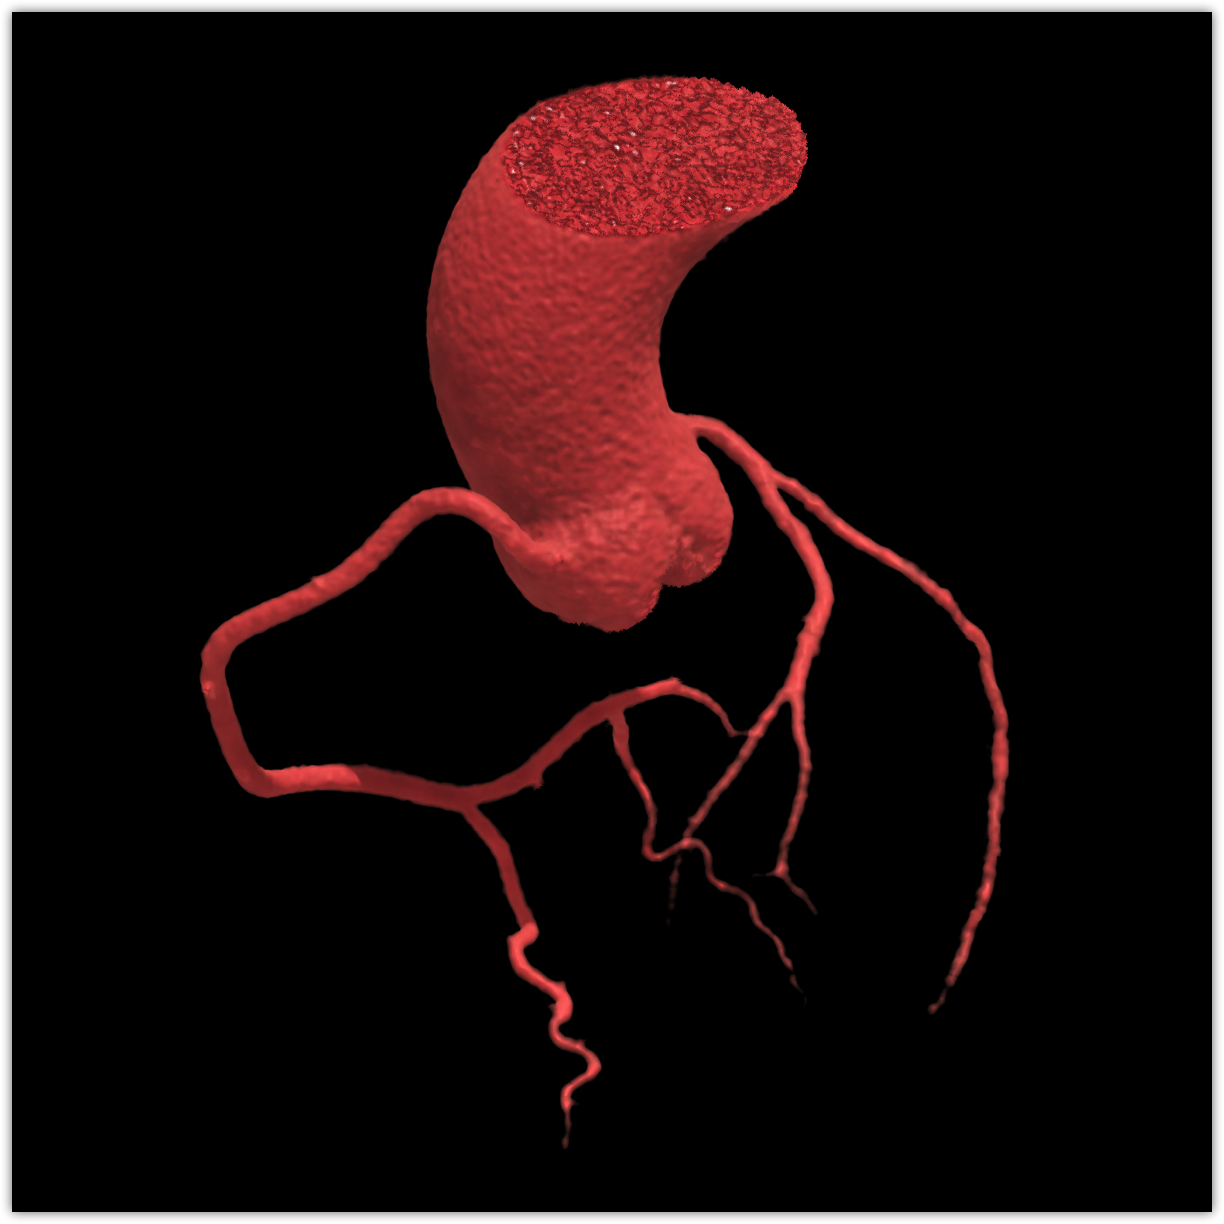

We believe in keeping you as healthy as possible. One of the ways we do this is by checking for heart disease with a Coronary CT Angiogram (CCTA) — a non-invasive scan that can see disease in your heart vessels even if you have no symptoms.

Preventive Cardiology Screening

Heart disease is the #1 cause of death in the United States.

Most people have no symptoms until it’s too late. A Coronary CT Angiogram (CCTA) lets us see disease in the vessels of your heart — before a heart attack happens.

LAD scan

Aorta scan

Coronaries scan

Right coronary scan